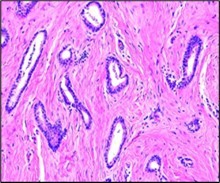

Figure 1.Tubular carcinoma delineating tubules layered by cuboidal to columnar epithelial cells impregnated with miniature to intermediate nuclei, apical snouts and surrounding desmoplastic stroma 7.

Around > 90% of tumefaction is comprised of miniature, ovoid or angulated tubules demonstrating open lumens. Neoplastic tubules are coated by singular layer of cuboidal to columnar epithelial cells impregnated with uniform, miniature to intermediate, low grade nuclei. Frequently, tumour cells display apical cytoplasmic tufts or snouts. Intraluminal secretion or calcification may be discerned. Neoplastic tubules appear devoid of encompassing myoepithelial cells.

Mitotic activity is minimal. Neoplasm is devoid of significant cytological atypia, multi-layering or enhanced mitotic activity 3, 4. Neoplastic cells appear immune reactive to oestrogen receptors (ER) and immune non reactive to HER2.

Two dimensional microscopic features and three dimensional modelling studies exhibit a neoplastic structure simulating a ‘necklace’ configured of string of beads wherein neoplastic tubules are visualized as blebs with solid cellular cords appearing as intervening bridges. Generally, continuous or branching tubules are absent. Surrounding stroma is desmoplastic or appears fibro-elastotic 3, 4. Frequently, neoplasm represents as non-obligate precursor of lesions as